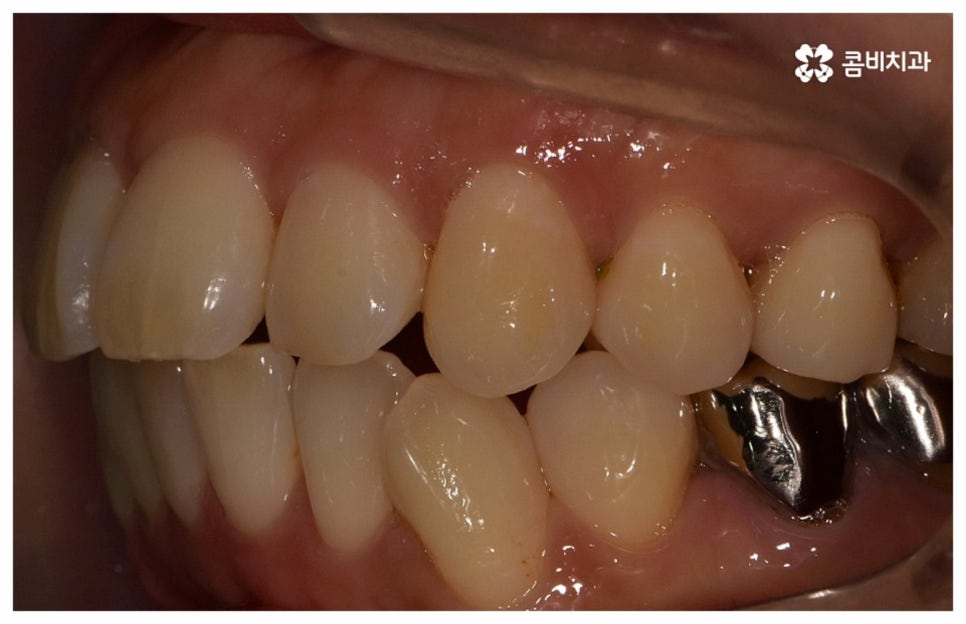

그래서인지 자기 관리의 일환으로 외모를 가꾸고 치아 건강을 증진시키기 위해 중년치아교정 을 고려하시는 분들도 늘어나고 있어요. 치열이 삐뚤어지고 교합이 잘 맞지 않는다면 교정 치료를 통해 이를 바로잡아 저작 기능을 향상시키고 발음을 정확하게 할 수 있으며, 심미적으로도 호감가는 인상을 만들고 추후 치아 관리도 보다 수월하게 할 수 있도록 도움을 받을 수 있기 때문에 이에 대한 수요가 많아지고 있는 거예요.

교정의 경우 보통 1년 반에서 2년 정도로 짧지 않은 기간이 걸리기 때문에 장치가 겉으로 드러나는 것에 대해 부담을 느끼시는 중장년분들이 많이 있습니다. 하지만 환자분들의 상황에 따라 부정 교합 정도가 심각하지 않고 골격적인 원인이 크지 않다면 6~8개월 정도 소요되는 부분 교정으로 필요한 부위만 보다 빠르고 간편하게 바로잡을 수 있으니 먼저 검진부터 진행해 보시길 권유드리고 있어요.

위 사진은 환자분의 동의를 받아 이해를 돕기 위한

사진이며, 실제 치료 결과는 다를 수 있습니다.